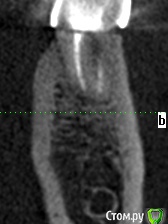

meld Опубликовано 7 ноября, 2017 Поделиться Опубликовано 7 ноября, 2017 Здравствуйте! Чуть больше года назад заболел 36 зуб. Я его пролечил с диагнозом периодонтит. 37 зуба нет. Было принято решение поставить мост с опорой на 36 и 38 зубы. 38 зуб был депульпирован в январе 2017 г. В мае 2017 я поставил мост. Вчера 38 зуб стал болеть при жевании. Боль не сильная, ломящая, через некоторое время проходит. Сегодня съездил в клинику, где лечил зубы, на осмотр. Осмотр ничего не выявил. Сделали прицельный снимок - по словам врачей (а их было двое) криминала тоже нет. Показал им свою томограмму - там тоже (по их словам) ничего нет. Посмотрите, пожалуйста, что не так. СпасибоСрезы 36 зуба Ссылка на комментарий